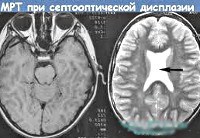

Q04.4 Септооптическая дисплазия